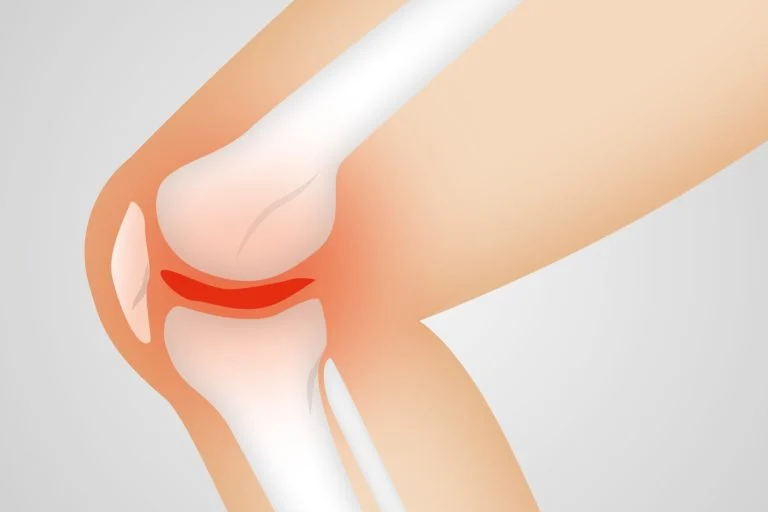

Bóle stawów to częsta dolegliwość po intensywnej aktywności fizycznej. Chcąc szybko schudnąć lub zbudować masę mięśniową, nierzadko zapominamy o tym, by zadbać o stawy. Bóle są zazwyczaj skutkiem błędów popełnianych w czasie ćwiczeń, ale też z wiekiem kondycja stawów pogarsza się, dlatego potrzebują one dodatkowego wsparcia.

To białko stanowiące znaczną część białek w naszym ciele, w około 30%. Jest on głównie obecny w strukturach takich jak ścięgna, kości i skóra. Składa się w większej części z dwóch aminokwasów: proliny i glicyny, a także z lizyny i innych składników. Do wytwarzania kolagenu organizm potrzebuje składników, takich jak witamina C, żelazo, mangan, cynk i krzemionka. Odgrywa kluczową rolę w utrzymaniu zdrowych stawów. Buduje chrząstkę stawową, a ponadto wspomaga produkcję mazi stawowej.

Jest ona niezbędna do tłumienia wstrząsów i zmniejszania tarcia między kośćmi podczas wykonywania ruchów. Kolagen jest niezbędny do regeneracji stawów, szczególnie w przypadku występowania mikrourazów podczas aktywności fizycznej. W chrząstkach stawowych występuje kolagen typu II i takiego najlepiej szukać w myśląc o suplementacji kolagenem, jeśli chcemy zadbać o stawy.